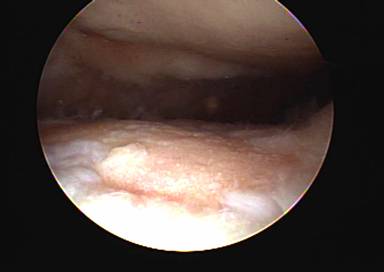

When exercises fail to improve the knee then surgery may be indicated if the symptoms are significant enough to alter activities. The most common arthroscopic surgical procedures to treat chondromalacia include chondroplasty and microfracture / abrasion procedure. A chondroplasty involves smoothing out roughened surface cartilage which can decrease friction forces on the surface cartilage and decrease symptoms of chondromalacia. An abrasion or microfracture is most useful when there is a small contained area of exposed bone or complete loss of surface cartilage. During this procedure the bone is tapped with a pick-type tool which causes bleeding in the area of exposed bone. This blood from deep inside the bone carries stem cells which can cause the bone to grow a scar type cartilage. This scar cartilage has been shown to be very effective in reducing knee pain in several orthopedic studies.